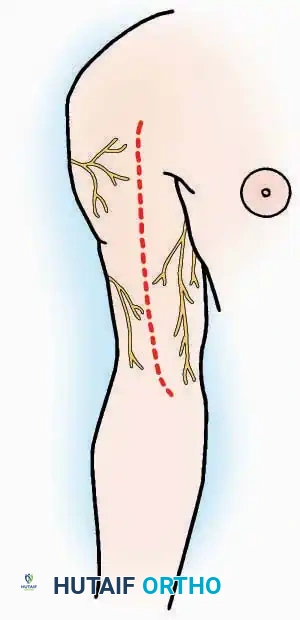

A pneumatic tourniquet should be universally employed in extremity surgery unless specifically contraindicated (e.g., severe peripheral vascular disease, sickle cell trait, or compromised soft-tissue envelopes). The exsanguinated, dry field facilitates precise dissection, minimizes traumatic tissue handling, and significantly reduces operative time. Furthermore, a bloodless field is critical for the reliable identification and preservation of delicate cutaneous nerves, which often serve as anatomical landmarks for deeper internervous planes.

* Nerve Protection: The sural nerve crosses the proximal and distal limbs of this approach. It must be identified and protected within the anterior flap.

* Neurovascular Warning: Meticulously identify and protect the medial calcaneal nerve and the nerve to the abductor digiti minimi (first branch of the lateral plantar nerve), which are highly vulnerable during inferior retraction.

* Nerve Protection: Retract the skin edges carefully. Identify and protect the intermediate dorsal cutaneous branches of the superficial peroneal nerve (SPN), which frequently cross the distal aspect of this incision.

* Superficial Dissection: Incise the superficial fascia. Identify and protect the superficial peroneal nerve branches laterally and the saphenous nerve medially.